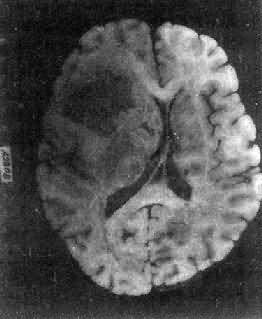

肉眼观,肿为数厘米的结节至巨大块状。分化较好的肿,境界不清;而分化程度较低的肿则境界分明。体灰白色。质地视肿内胶质纤维多少而异,或硬、或软、或呈胶冻状外观,并可形成大小不等的囊腔。由于肿的生长、占位和邻近脑细胞的肿胀,脑的原有结构因受挤压而扭曲变形(图16-23)。

图16-23 星形胶质细胞

左大脑半球肿胀,肿边界不清,部分呈胶冻状